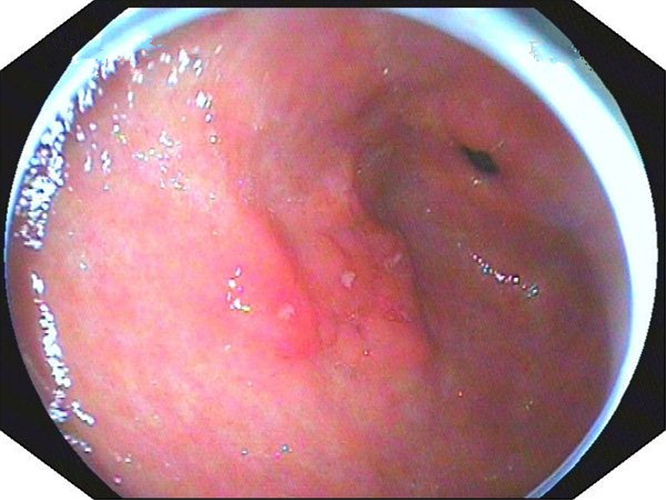

中型淺表萎縮慢性胃炎

萎縮淺表性慢性胃炎

萎縮性的慢性胃炎

萎縮性慢性胃炎

萎縮慢性胃炎

萎縮出血性慢性胃炎

輕型淺錶慢性胃炎

輕型淺表型慢性胃炎

淺表型糜爛出血慢性胃炎

淺表型糜爛慢性胃炎